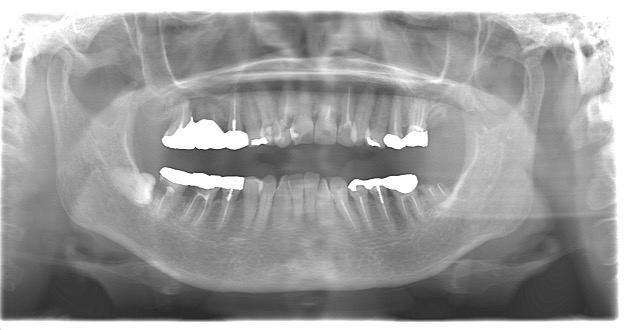

パノラマX線・レントゲン写真

多数歯にわたり虫歯の治療を行なった形跡がある。

これはセルフケア・治療方法の限界・噛み合わせによるものと考えられます。

パノラマX線

歯列の改善が認められ、欠損部分には必要な本数のインプラントを埋入しました。

咬合の安定と審美性の向上のためにセラミックにて被せ物を装着しています。